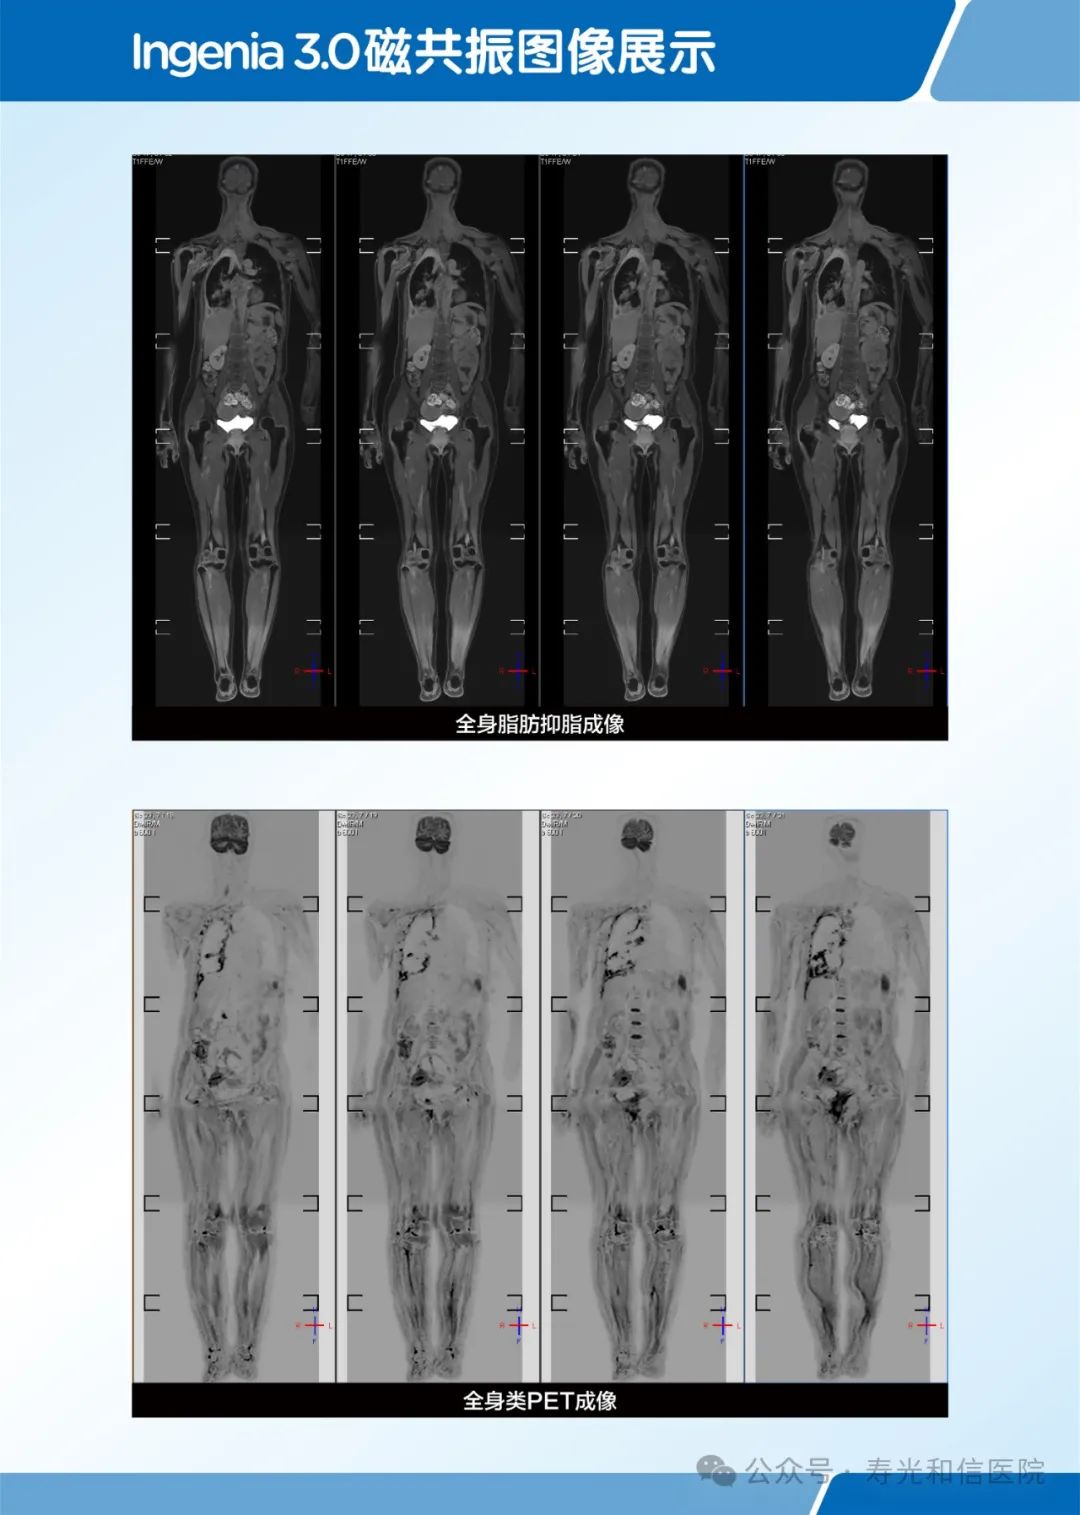

直接冠状位全身类 PET 成像

在全身弥散加权成像的同时,可进行磁共振全身扫描,增加肿瘤检出敏感性。

临床应用范围:寻找恶性肿瘤原发灶;恶性肿瘤分期;全身转移灶筛查;淋巴结转移筛查;术后放化疗疗效监测;恶性血液肿瘤疗效观察;体检与肿瘤筛查。